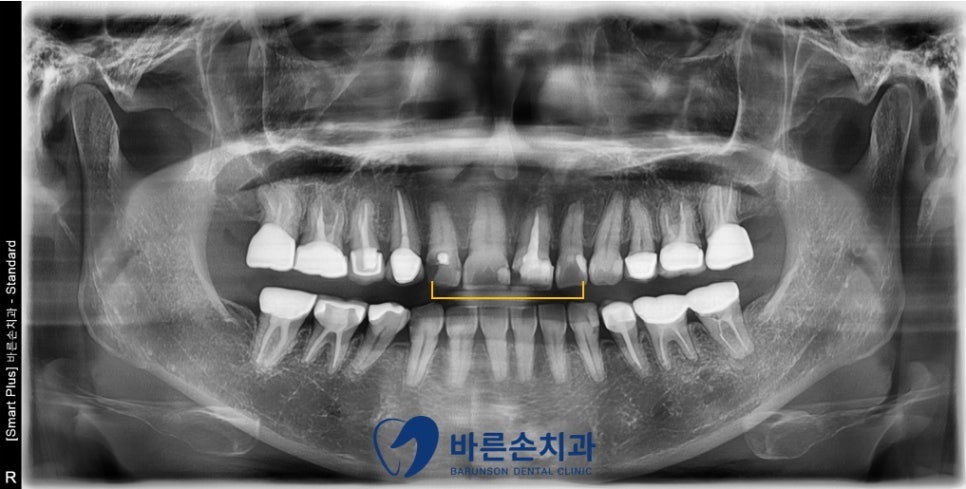

위 앞니에 충치가 심해요!!

위 앞니가 충치가 생겨 오셨습니다.

정면에서 보았을 때, 위 앞니가 충치로 인해

시커멓게 보이는 부분이 있습니다.

치아의 옆면, 뒷면에 충치가 있어 비쳐 보입니다.

과거 충치치료, 신경치료를 한 흔적이 있고,

그 주위로 2차 우식이 진행된 상태 입니다.

충치를 모두 제거하고, 크라운 치료를 하기로 합니다.

충치가 심하여, 치아가 얼마 안 남게 되는 치아는

신경치료 및 포스트 치료를 병행합니다.